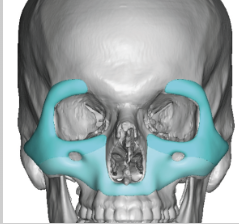

all of them share one thing, their midface is extremely projected. No smile lines, no sunken areas on their face that can create folds. Can midface implants achieave this effect? Extreme benefits + its not as invasive as bimax and cheap.